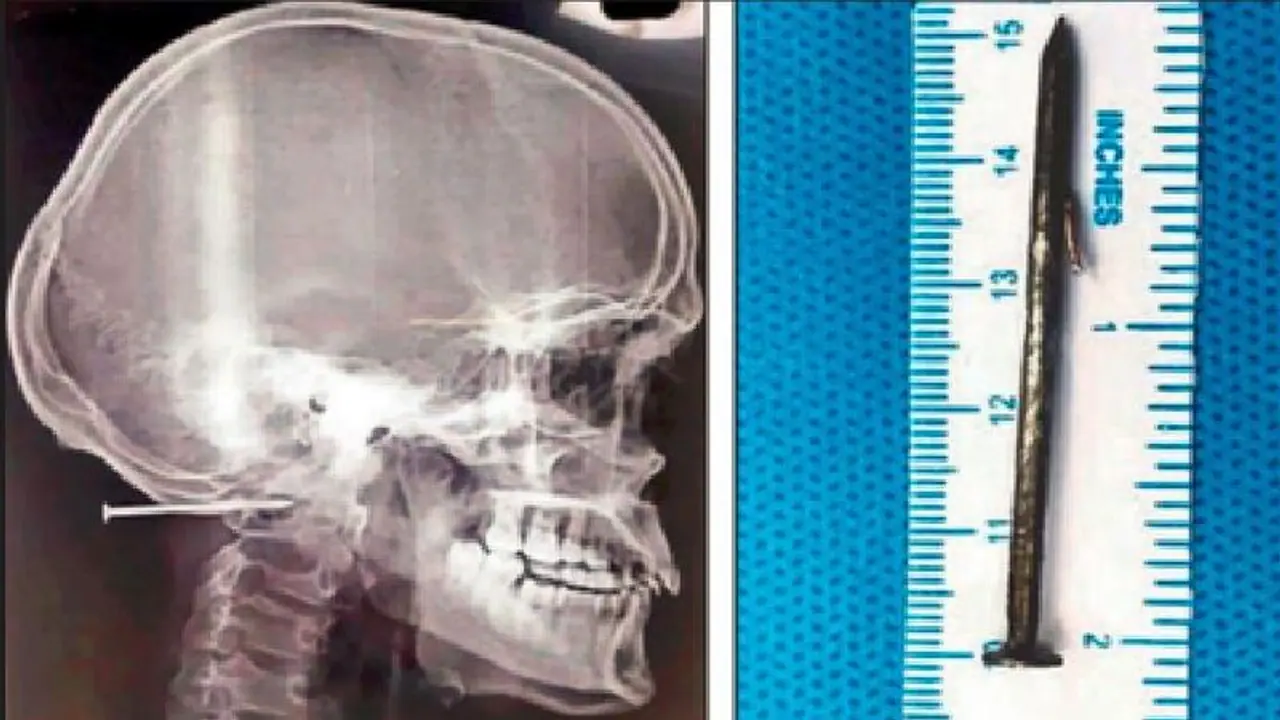

ಚೆನ್ನೈ: ಕೆಲಸದ ವೇಳೆ ಅಚಾನಕ್ ಆಗಿ ಕಾರ್ಮಿಕನ ತಲೆ ಹೊಕ್ಕಿದ್ದ 2 ಇಂಚು ಉದ್ದದ ಮೊಳೆಯೊಂದನ್ನು ವೈದ್ಯರು ಐದು ಗಂಟೆಗಳ ಸುದೀರ್ಘ ಶಸ್ತ್ರಚಿಕಿತ್ಸೆಯ ಬಳಿಕ ಹೊರ ತೆಗೆದಿದ್ದಾರೆ. ಚೆನ್ನೈನ ಖಾಸಗಿ ಆಸ್ಪತ್ರೆಯಲ್ಲಿ ಈ ಶಸ್ತ್ರಚಿಕಿತ್ಸೆ ನಡೆದಿದೆ. ಫ್ಯಾಕ್ಟರಿಯೊಂದರಲ್ಲಿ ಕೆಲಸ ಮಾಡುತ್ತಿದ್ದ 23 ವರ್ಷದ ಕಾರ್ಮಿಕನಿಗೆ ಕೆಲಸ ಮಾಡುತ್ತಿದ್ದ ವೇಳೆ ಅಚಾನಕ್ ಆಗಿ ಮೊಳೆಯೊಂದು ತಲೆ ಹೊಕ್ಕಿದೆ. ಸಹ ಕಾರ್ಮಿಕನ ಮೊಳೆ ಹೊಡೆಯುವ ಗನ್ ಅಚಾನಕ್ ಆಗಿ ಆನ್ ಆದ ಪರಿಣಾಮ ಈ ಘಟನೆ ನಡೆದಿದೆ. ಜುಲೈ 4ರಂದು ಈ ಘಟನೆ ನಡೆದಿದ್ದು, ತಡವಾಗಿ ಬೆಳಕಿಗೆ ಬಂದಿದೆ.

ಜುಲೈ 4 ರಂದು ಚೆನ್ನೈನ (Chennai) ನವಲೂರಿನಲ್ಲಿರುವ ಫ್ಯಾಕ್ಟರಿಯಲ್ಲಿ ಈ ಘಟನೆ ನಡೆದಿದ್ದು, ಬ್ರಹ್ಮನ ಸಹೋದ್ಯೋಗಿ ಮರದ ಬಾಕ್ಸೊಂದನ್ನು ಮೊಳೆ ಹೊಡೆಯುವ ಗನ್ನಿಂದ ಸೀಲ್ ಮಾಡುತ್ತಿದ್ದು, ಈ ವೇಳೆ ಅದೇ ಸ್ಥಳದಲ್ಲಿ ಬ್ರಹ್ಮ ನೆಲಹಾಸನ್ನು ಗುಡಿಸುತ್ತಿದ್ದ, ಈ ವೇಳೆ ಬ್ರಹ್ಮನಿಗೆ ತಲೆಯ ಹಿಂಭಾಗದಲ್ಲಿ ತಡೆದುಕೊಳ್ಳಲಾಗದಷ್ಟು ನೋವಾಗಲಾರಂಭಿಸಿದೆ. ಜೊತೆಗೆ ರಕ್ತಸ್ರಾವವಾಗಲು ಶುರುವಾಗಿದೆ. ಆ ಮಹಡಿಯಲ್ಲಿದ್ದ ಸಿಬ್ಬಂದಿ ಆತನನ್ನು ಸಮಾಧಾನಪಡಿಸಲು ಮುಂದಾಗಿದ್ದಾರೆ. ಆತನ ಕುತ್ತಿಗೆ ಹಾಗೂ ತಲೆಯನ್ನು ಸಂಪರ್ಕಿಸುವ ನಡುವಿನ ಜಾಗದಲ್ಲಿ ಸಣ್ಣ ಬ್ಯಾಟರಿಯಷ್ಟು ಉದ್ದ ಗಾತ್ರದ ಮೊಳೆಯೊಂದು ಸೇರಿಕೊಂಡಿತ್ತು. ಆದರೆ ಈ ನೋವಿನಲ್ಲೂ ಆತನಿಗೆ ಪ್ರಜ್ಞೆ ತಲುಪಿರಲಿಲ್ಲ.

ಆದರೆ ಮೊಳೆ ಆತ ಚರ್ಮದ ಹಂತಕ್ಕಿಂತ ಅರ್ಧ ಇಂಚು ಒಳಗೆ ಕ್ರಾನಿಯೋವರ್ಟೆಬ್ರಲ್ ಜಂಕ್ಷನ್ ಎಂಬ ಸಂಕೀರ್ಣ ಪರಿವರ್ತನೆಯ ವಲಯವನ್ನು (ಕಪಾಲ ಮತ್ತು ಬೆನ್ನುಮೂಳೆಯ ಕೀಲಿನ ನಡುವೆ) ಹೊಕ್ಕಿತ್ತು. ಈ ಸ್ಥಳ ವಿಭಿನ್ನ ಅಂಶಗಳ ಸಂಕೀರ್ಣ ಸಮತೋಲನವನ್ನು ಒಳಗೊಂಡಿದೆ ಮತ್ತು ಎಡ ಕಶೇರುಕ ಅಪಧಮನಿಯ ಹತ್ತಿರದಲ್ಲಿದೆ. ಹೀಗಾಗಿ ಯಾವುದೇ ಅಹಿತಕರ ಸ್ಥಿತಿಗೆ ಇದು ಕಾರಣವಾಗುತ್ತಿತ್ತು. ಒಂದು ಮಾತನಾಡುವುದಕ್ಕೆ ಕಷ್ಟವಾಗುವಂತಹ ಸ್ಥಿತಿ ಉಂಟಾಗುತ್ತಿತ್ತು. ಅಥವಾ ಸಾವಿಗೂ ಕಾರಣವಾಗುತ್ತಿತ್ತು. ಸ್ಕ್ಯಾನಿಂಗ್ ಚಿತ್ರಗಳು ಇದು ಸರಳವಾದ ಮೊಳೆಯಲ್ಲ ಎಂಬುದನ್ನು ತೋರಿಸುತ್ತಿತ್ತು. ಸುಲಭವಾಗಿ ಹೊರಬರಲು ಸಾಧ್ಯವಾಗದಂತ, ಅಥವಾ ಒಮ್ಮೆ ಮರಕ್ಕೆ ಇದನ್ನು ಹೊಡೆದರೆ ಸುಲಭವಾಗಿ ತೆಗೆಯಲಾಗದಂತೆ ಡಿಸೈನ್ ಅನ್ನು ಈ ಮೊಳೆ ಹೊಂದಿತ್ತು ಎಂದು ವೈದ್ಯರಾದ ಅಂಬುಸೆಲ್ವಂ ಹೇಳಿದರು.

ನಂತರ ರೋಗಿಯನ್ನು ಮುಖ ಕೆಳಗೆ ಮಾಡಿ (ಅಂಗಾತ) ಮಲಗಿಸಿ ಶಸ್ತ್ರಚಿಕಿತ್ಸೆ ಮಾಡಲು ನಿರ್ಧರಿಸಲಾಯ್ತು. ಇದಕ್ಕಾಗಿ ವಿಶೇಷವಾದ ಡೈಮಂಡ್ ಬುರ್ ಎಂಬ ನ್ಯೂರೋಸರ್ಜರಿ ಉಪಕರಣ ವನ್ನು ಬಳಸಿ ಮೊಳೆ ಇರುವ ಜಾಗದ ಸುತ್ತ ಡ್ರಿಲ್ (ಕೊರೆಯುವುದು) ಮಾಡಲಾಯಿತು. ನಂತರ ಮೊಳೆಯ ಹಿಡಿತಲೆ ಕಾಣಿಸಿತ್ತು. ನಂತರ ಮತ್ತೆ ಸೂಕ್ಷ್ಮವಾಗಿ ಡ್ರಿಲ್ ಮಾಡಿ ಮೊಳೆಯನ್ನು ಹೊರಗೆಳೆಯಲಾಯಿತು.